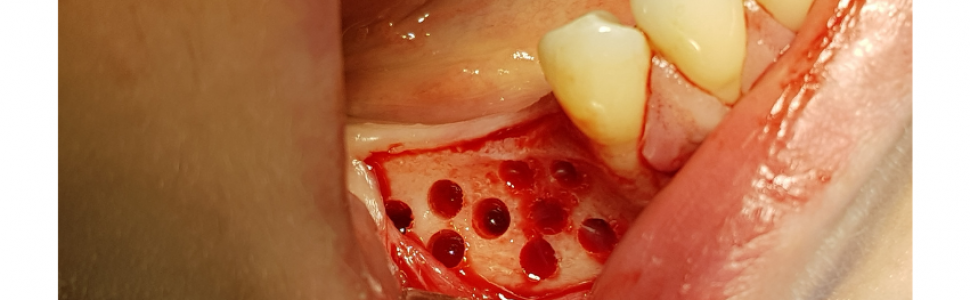

Następnie wykonano otwory trepanacyjne w blaszce korowej kości o średnicy około 3 mm dochodząc do kości gąbczastej (ryc. 7). Taka średnica jest zalecana przez producenta dla lepszej retencji i utrzymania kształtu cementu regeneracyjnego w takim ubytku. Następnie po aktywacji umieszczono i uformowano cement na przygotowanej powierzchni kości (2 cm3) (ryc. 8).

Ryc 8. Uformowanie cementu na powierzchni wyrostka. Ryc 9. Zaopatrzenie rany.